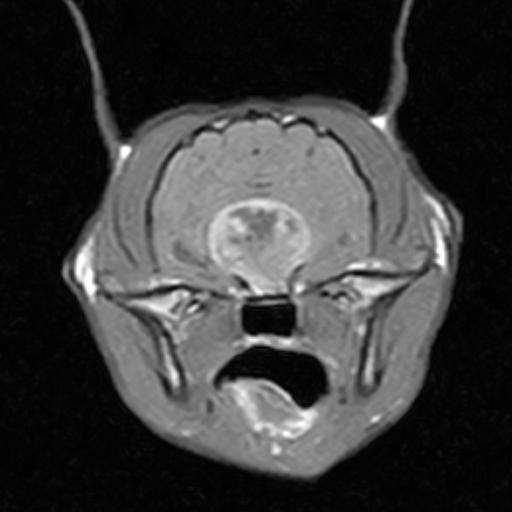

In order to diagnose brain tumours, CT-scans or MRI-scans are used to image the brain. Despite the fact that these tests are very good at detecting the presence of a mass in the brain, they are very poor at identifying its exact nature (i.e. whether it is a tumour, inflammation, or bleeding within the brain).

When it comes to people, a biopsy of a brain tumour is the preferred way to determine the type of tumour and other information regarding treatment and prognosis. Normally, we do not recommend brain biopsy in animals since it is a very invasive and potentially risky procedure. A veterinary neurologist will often diagnose a tumour type based on key features on scans. This approach has limitations, so it is difficult to provide accurate information regarding treatment and prognosis.

The primary form of brain tumour occurs when brain tissue grows uncontrollably. There are several types of primary brain tumours, including those formed in the lining of the brain’s surface (meningiomas), the lining of the ventricle (ependymomas), the choroid plexus (choroid plexus tumours), and the brain parenchyma itself (gliomas).